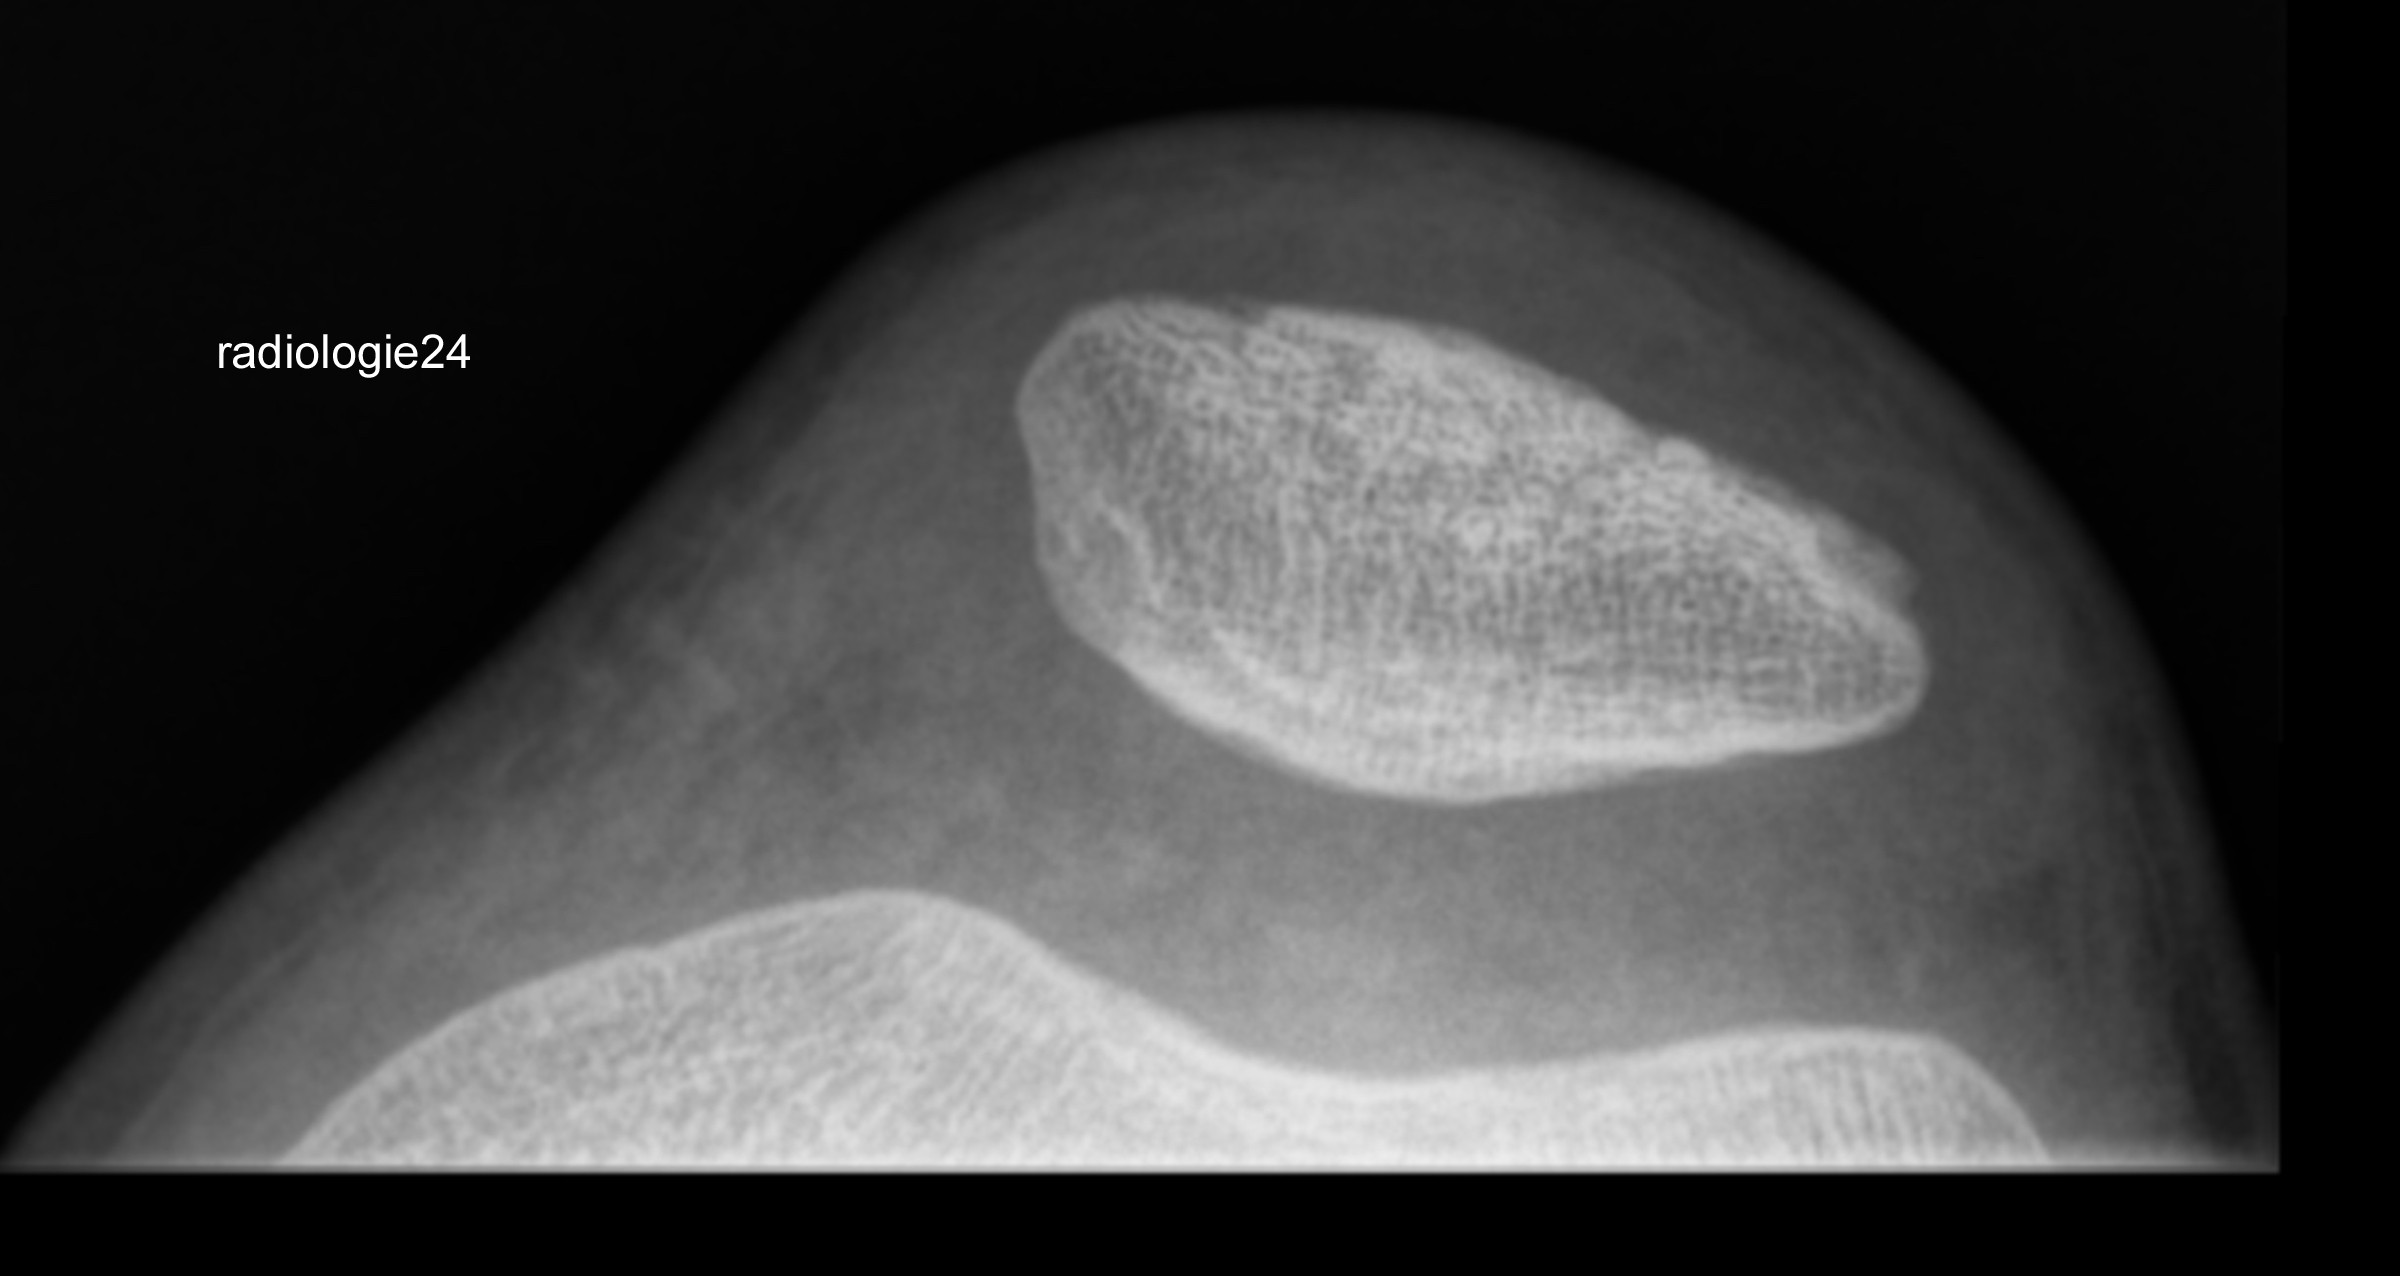

Röntgenfall des Monats März 2018 mit Auflösung

10 jähriger Patient Z.n.Sturz. Schmerzen im Bereich des Kniegelenks Ihre Diagnose?